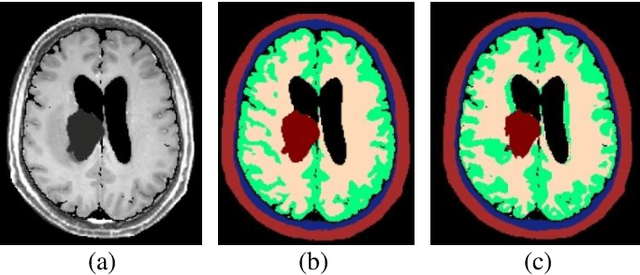

Abstract:Tumor treating fields (TTFields) is an FDA approved therapy for the treatment of Gliobastoma Multiform (GBM) and currently being investigated for additional tumor types. TTFields are delivered to the tumor through the placement of transducer arrays (TAs) placed on the patient scalp. The positions of the TAs are associated with treatment outcomes via simulations of the electric fields. Therefore, we are currently developing a method for recommending optimal placement of TAs. A key step to achieve this goal is to correctly segment the head into tissues of similar electrical properties. Visual inspection of segmentation quality is invaluable but time-consuming. Automatic quality assessment can assist in automatic refinement of the segmentation parameters, suggest flaw points to the user and indicate if the segmented method is of sufficient accuracy for TTFields simulation. As a first step in this direction, we identified a set of features that are relevant to atlas-based segmentation and show that these are significantly correlated (p < 0.05) with a similarity measure between validated and automatically computed segmentations. Furthermore, we incorporated these features in a decision tree regressor to predict the similarity of the validated and computed segmentations of 20 TTFields patients using a leave-one-out approach. The predicted similarity measures were highly correlated with the actual ones (average abs. difference 3% (SD = 3%); r = 0.92, p < 0.001). We conclude that quality estimation of segmentations is feasible by incorporating machine learning and segmentation-relevant features.